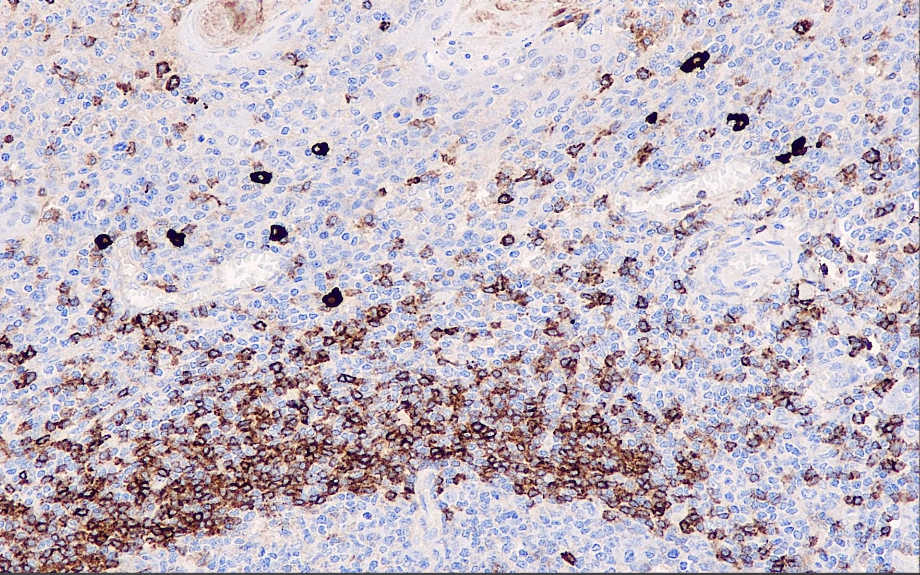

Positive control: tonsils

IgD can label the δ chain of IgD in cells, assisting in the differential diagnosis of lymphoma, plasma cell tumor and B-cell-derived Hodgkin's lymphoma. It is mainly used in the research of lymphatic system tumors.

IgD antibody reagents can specifically bind to IgD molecular antigens. Immunohistochemical kits containing IgD antibody reagents are suitable for the auxiliary diagnosis of lymphoma, plasmacytoma and B-cell-derived Hodgkin's lymphoma.